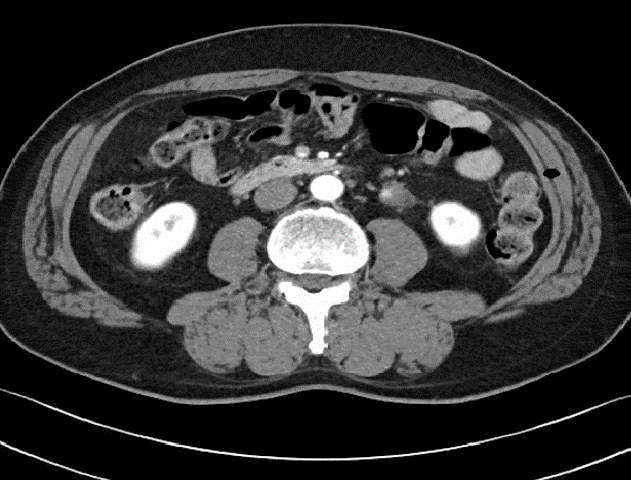

We decided kidney transplantation between the married couple. The living donor was 61 year old male, and his CT angio abdomen scan showed about 0.6 cm stone at left proximal ureter, and small size periureteral low density lesion at the left proximal ureter.

In operation, we found of a lump of soft tissue in periureter, measuring 4.5x4x2.5cm, yellowish adipose tissue-like appearance. Frozen specimen cut-surface showed cystic appearance filled with yellowish necrosis like material, and was diagnosed as parasite infection, morphologically paragonimiasis.